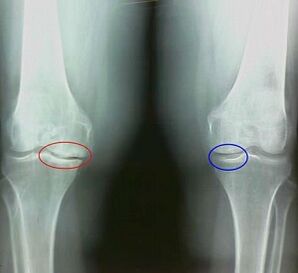

Arthrosis is a degenerative-divophical process associated with the destruction of the articulation cartilage tissue.The cartilage is gradually destroyed, dry, the distance between the bones of the joint decreases, which is the cause of pain.In severe shapes, destruction affects bones.They become more porous, they lose their density, they become fragile.

For example, what is the difference between arthritis and osteoarthritis of the knee joint?With arthritis, the synovial layer of joint tissues occurs.This causes an increase in joint temperature.

The articulation increases, a persistent pain syndrome is developed, which intensifies during movement.With osteoarthritis, pain occurs only after physical activity, you can listen to a characteristic crunch or clicks in the joint, gradually the joint is deformed and loses mobility.

- The pains appear after physical activity, with sudden movements, turns, inclinations, after rest, pain passes;

- A characteristic crunch is observed in the joints;

- The pain after prolonged rest, which happens within 15-20 minutes of mobility (this is associated with the stagnant phenomena that occur in the joint);

- Concerned about the pain of opaque night pain that occurs due to venous stagnation;

- The inflammatory form of pathology is accompanied by edema and pain;

- The articulation is deformed, its mobility decreases.